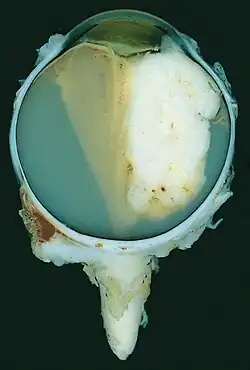

| A pathology specimen of a retinoblastoma tumor from an enucleated eye of a 3-year-old female | |

Gross and microscopic appearances of retinoblastoma are identical in both hereditary and sporadic types. Macroscopically, viable tumor cells are found near blood vessels, while zones of necrosis are found in relatively avascular areas. Microscopically, both undifferentiated and differentiated elements may be present. Undifferentiated elements appear as collections of small, round cells with hyperchromatic nuclei; differentiated elements include Flexner-Wintersteiner rosettes, Homer Wright rosettes,[31] and fleurettes from photoreceptor differentiation.[32]

Large exophytic white tumor with foci of calcification producing total exudative retinal detachment -